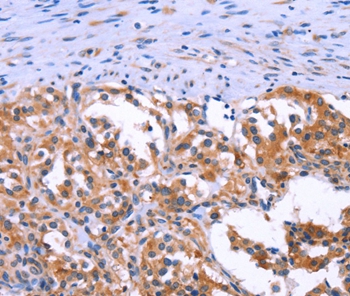

![IHC-P analysis of human gastrointestinal stromal tumor (GIST) tissue using GTX04369 TMEM16A antibody [MSVA-201M] HistoMAX?. DOG1 Tumor periphery of a GIST showing intensive TMEM16A staining in all tumor cells.](https://www.genetex.com/upload/website/prouct_img/normal/GTX04369/GTX04369_20230728_IHC-P_47_23072722_384.webp)